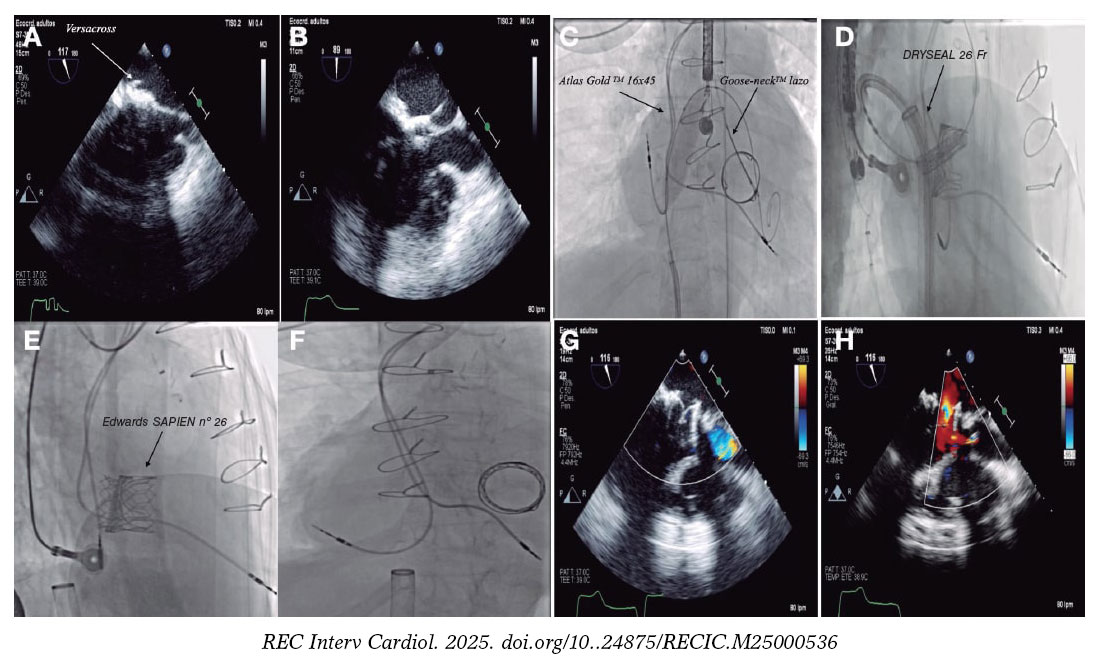

Mujer de 55 años con canal auriculoventricular incompleto con reparación del cleft mitral y cierre con parche del defecto tipo ostium primum y posterior implante de bioprótesis mitral (Carpentier PERIMOUNT 27, Edwards, EE.UU.) en la edad adulta. Evolucionó con episodios de aleteo auricular izquierdo y se decidió realizar una ablación retroaórtica del nódulo auriculoventricular, por imposibilidad de punción transeptal, con disección yatrogénica del tronco común izquierdo resuelta tras el implante de un stent farmacoactivo (figura 1A-D, vídeos 1 y 2 del material adicional). A lo largo del seguimiento presentó datos de degeneración protésica progresiva (figura 2A-B, vídeos 3 y 4 del material adicional), por lo que se decidió llevar a cabo un implante percutáneo de prótesis mitral valve-in-valve. Se procedió con punción transeptal del parche gravemente calcificado (figura 2C-D) con sistema Versacross (Boston Scientific, EE.UU.) y mediante un catéter deflectable se avanzó una guía de alto soporte que fue capturada en el ventrículo izquierdo, estableciendo un circuito venoarterial. Se realizó septostomía con catéter balón Atlas Gold 16 × 45 mm (BD, EE.UU.), y con gran dificultad, dada la complejidad anatómica, se avanzó una vaina de 26 Fr DRYSEAL (Gore, EE.UU.) hasta la aurícula izquierda, a través de la cual se implantó una bioprótesis SAPIEN 3 Ultra 26 (Edwards, EE.UU.) con inflado nominal + 2 cm3. Se observó una buena expansión, con ligera protrusión en el ventrículo izquierdo sin conflicto con el tracto de salida (figura 3A-D, vídeo 5 del material adicional). Se dio el alta hospitalaria a la paciente con una función protésica normal que se mantenía al año de seguimiento (vídeo 6 del material adicional). La paciente firmó el consentimiento informado.

Figura 1.